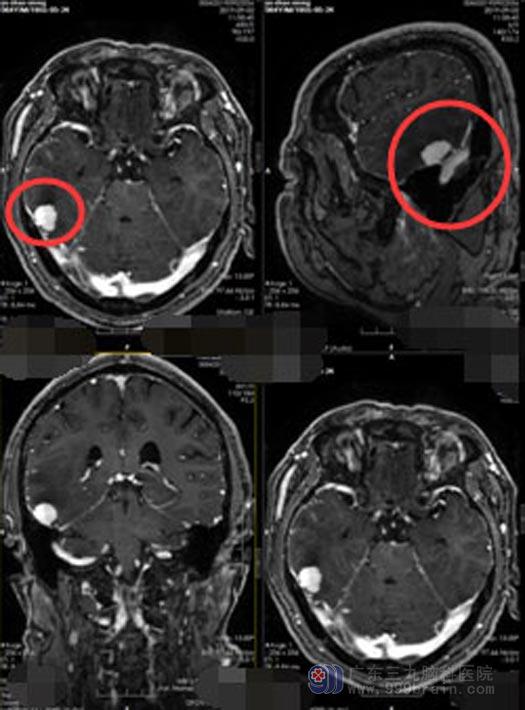

最近半个月,头痛开始加重,感觉天旋地转、难以忍受,并且呕吐了多次。儿女们觉得不太对劲,送余老伯到当地医院,头颅MR提示:右侧颞部占位。

急坏了家人带着余老伯跑了多家知名的三甲医院,可得到的答复不是床位紧张就是医院条件有限。后来通过朋友的推荐,最终来到广东三九脑科医院神经外五科。进一步头颅CT检查提示:右侧颞叶占位,考虑脑膜瘤。完善术前检查后,医院副院长、神经外五科主任鲁明带领团队迅速为余老伯制定了手术方案,决定在导航下行“右侧颞叶肿瘤切除术”。手术进行得十分顺利;术后第三天,余老伯就可以下床活动、普通饮食;术后第十天,余老伯就康复出院了。

▲手术前